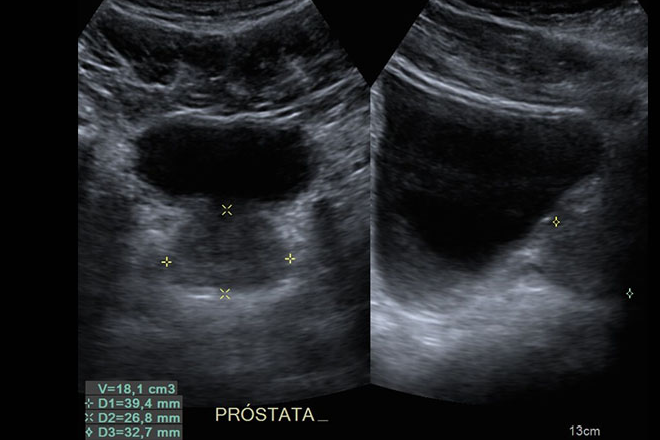

De los 93 pacientes encuestados, solo 57 cumplieron criterios. La edad promedio fue 71 años, con un rango de 51 a 83 años. La media de antígeno prostático específico (APE) fue 95.67 ng/mL (intervalo de 4.4 a 1063 ng/mL). La distribución de Gleason fue baja (6.25%), intermedia (56.25%) y alta (37.5%). Los tratamientos iniciales fueron cirugía radical (45.6%), tratamiento hormonal (42.1%), radioterapia (7%) y vigilancia (5.2%). El seguimiento promedio fue 47.7 meses. Los resultados del cuestionario EPIC-2002 fueron: promedio global de 3,196 puntos, síntomas urinarios 856 puntos, intestinales 1,180 puntos, sexuales 305 puntos y hormonales 823 puntos.